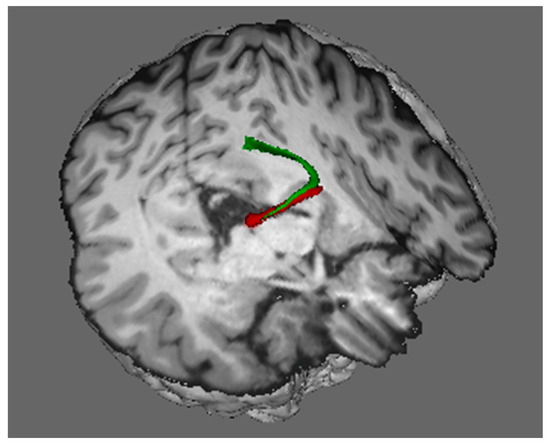

Now, let us take a look under the hood at the neural machinery that implements this ability to see a stable visual world when we move our eyes. Since the superior colliculus is the final arbiter for selecting a saccade target and for generating commands to move the eyes, the collicular neurons generating those commands to the brainstem send axon collaterals upstream to signal the dorsal visual stream that the eyes have moved. Sommer and Wurtz (2008) demonstrated, in monkeys, that these copies of the motor commands are transmitted to the frontal eye field via relay neurons in the lateral border of the mediodorsal nucleus of the thalamus. By inactivating thalamic neurons that receive copies of the eye movement signals from the colliculus, they confirmed that these neural signals from the colliculus are used to update the visual cortex that the eyes have moved. Sommer and Wurtz (2008) tested monkeys on the double-step saccade task before and after the inactivation of the thalamic neurons transmitting signals from the superior colliculus to the cortical frontal eye field. After this inactivation, the monkeys could not execute accurate saccades toward the second target (Sommer and Wurtz 2008). Figure 10 shows the pathway from the superior colliculus to the frontal eye fields in the human brain, and it shows the termination of this pathway in the frontal eye fields of both humans and monkeys.